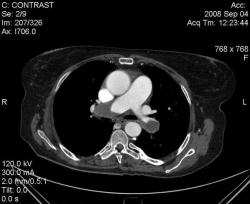

3аключение КТ что: далее цитирую "Патологические изменения в нижней доле правого лёгкого могут соответствовать остаточным явлениям перенесенной пневмонии, инфарктам лёгкого вследствие тромбоэмболии легочной артерии." это не заключение КТ по поводу ТЭЛА. Если пациент изначально направляется на КТ с подозрением на ТЭЛА, то и сьемка должан проводится по протоколу ТЭЛА (срезы 1 мм или ниже; болюс контраст; снимаем снизу вверх против тока крови). Я приведу ниже два скана разных пациентов с ТЭЛА:

скан 1: массивная тромбоэмболия обоих основных стволов.

скан 2: тромбоэмболия суб-сегментарных (!) веточек базальных сегментов левой нижней доли. Тромб указан красной стрелкой;нормальный сосуд белой.

Для справки: у меня мультидетекторный аппарат; 6-срезовой.